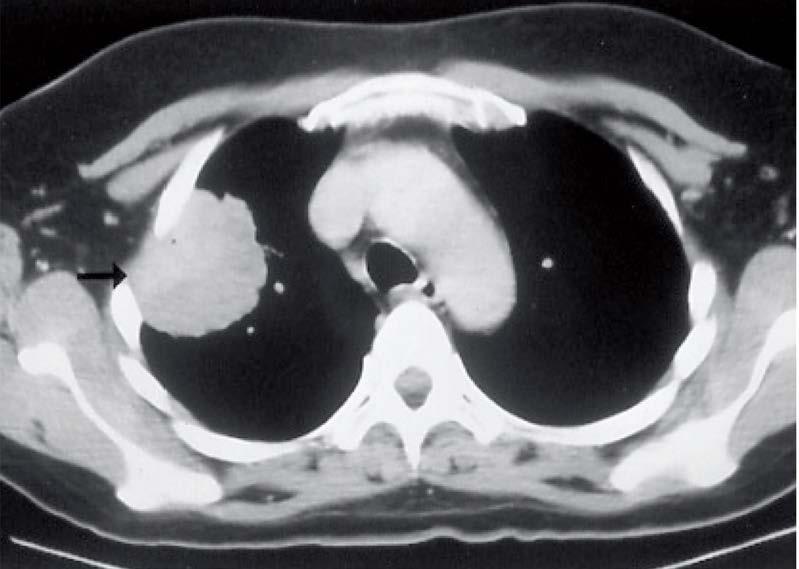

Mynd 6-1 Lítið lungnakrabbamein í hægra lunga (ör) sem fannst við skimun með tölvusneiðmyndum.

Með tilkomu tölvusneiðmyndatækni (TS) varð unnt að finna mun smærri hnúta í lungum en áður var mögulegt með hefðbundnum röntgenmyndum (mynd 6-1). Á síðustu áratugum hefur verið efnt til stórra framvirkra samstarfsverkefna, bæði í Bandaríkjunum og Evrópu. Fyrstu rannsóknir á skimun með TS voru gerðar í Japan og fyrsta alþjóðlega rannsóknin benti til þess að unnt væri að finna um